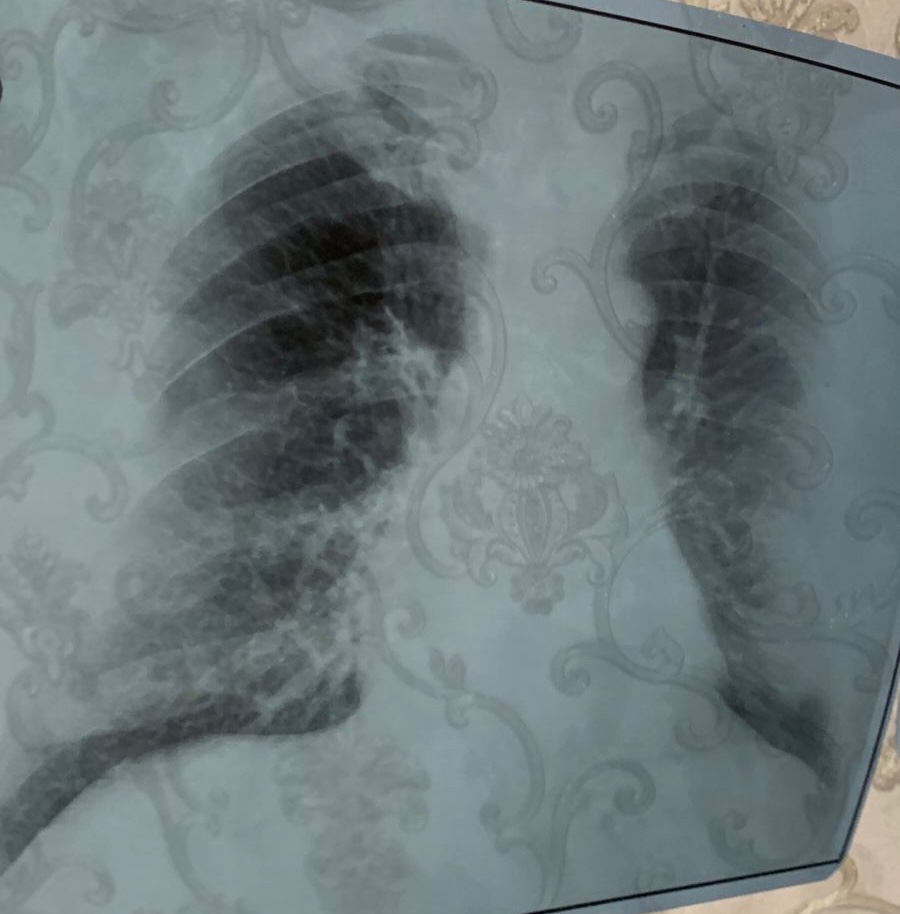

Здравствуйте. Прошу вас провести консультацию по рентгеновскому снимку органов грудной клетки моего отца. Ему 56 лет, в течение последних двух недель его беспокоит продолжительный кашель с отделением мокроты. Пожалуйста, оцените, имеются ли на снимке патологические изменения.